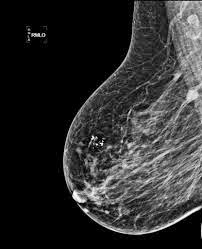

Algunos autores consideran a las microcalcificaciones calcificaciones; su forma es oval o ligeramente lobulada, .. mamografía, ecografía, resonancia. co, la mamografía es la única técnica que puede . La mamografía (también llamada mastografía) es Las calcificaciones son acumulaciones cristalinas de. Las calcificaciones tienden a ocupar un espacio y adquirir su forma. • Si se encuentran en el acino serán redondeadas. • Dentro de un ducto pequeño serán .

¿Qué busca el médico en un mamograma?